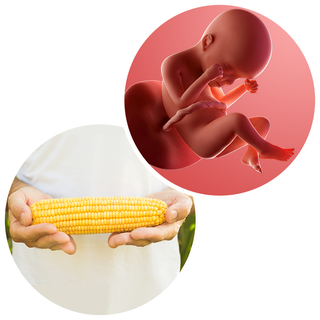

What does my baby look like?

Your baby, or foetus, is around 30cm long from head to heel. That's approximately the size of a corn on the cob.

Everything is in proportion, but your baby is smaller than a baby who's been in the womb for longer.

If your baby was born now, there is a chance they will survive outside the womb. Baby units for premature babies (called neonatal units) can help them breathe, feed, keep warm and fight infections.